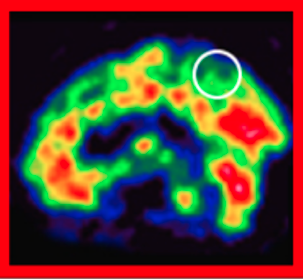

脳血流シンチグラフィは脳の血流状態を可視化する検査です。脳のどの部位で血流が保たれているか、あるいは低下しているのかを確認できます。

認知症の種類ごとに特徴的な血流低下パターンがあるため認知症の鑑別診断に役立ちます。

健康な人では、後部帯状回や楔前部および後頭葉などの血流が赤く映し出される。

アルツハイマー型認知症の人では、後部帯状回や頭頂葉内側の楔前部などで血流の低下がみられます